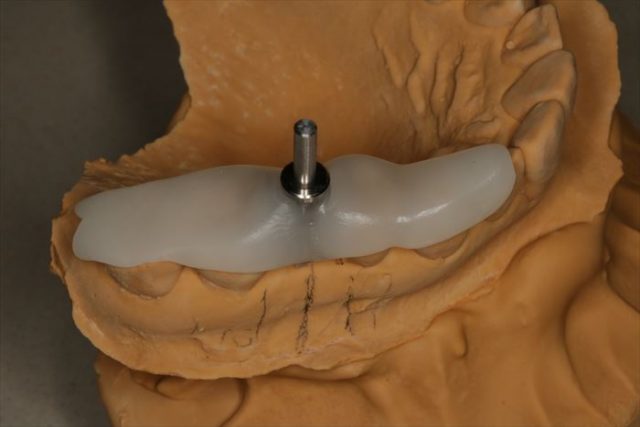

上下歯列の型取りとフェイスボウトランスファーを行い、上顎歯列と顎関節の関係を記録します。

フェイスボウの記録を利用して、咬合器に上下歯列模型をマウントしました。

模型上でシミュレーションしてサージカルステント(ドリルガイド)を作成し、準備は完了です。